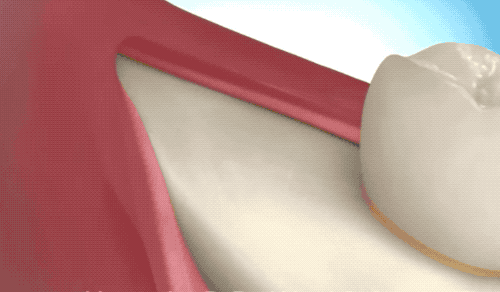

露出牙槽骨后,先削除一部分骨頭,露出躺臥如睡美人的橫阻生智齒...如果是已經(jīng)出肉的智齒,就沒(méi)這一步了。

請(qǐng)出那令人聞聲喪膽的牙科渦輪機(jī),先分割智齒,撬出塊頭過(guò)大的牙冠來(lái)...再把牙根磨切兩半,依次撬出來(lái)。當(dāng)然這樣的操作并不都是必須的,牙醫(yī)會(huì)依據(jù)當(dāng)時(shí)的可操作性去處理,畢竟每個(gè)哈姆雷特的橫阻生智齒也都可能長(zhǎng)得不一樣。